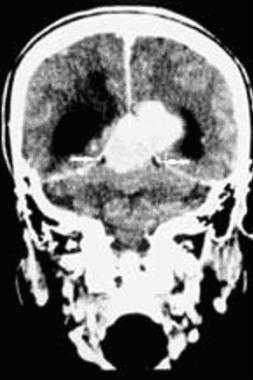

(Справа) МРТ Т1ВИ FS с КУ, аксиальная проекция. Менингиома яремного отверстия распространяется вниз, в сонное пространство. Обратите внимание, что сонная артерия расположена спереди от опухоли. Подобные опухоли происходят из клеток арахноидального эндотелия. Увеличиваясь в размерах, менингиома начинает спускаться в сонное пространство. (Слева) МРТ Т1ВИ FS с КУ, аксиальная проекция. Крупная, накаливающая контраст опухоль правого сонного пространства, смещающая сонную артерию кпереди. Обратите внимание, что участки выпадения сигнала отсутствуют. Этот признак помогает дифференцировать менингиому от более распространенной опухоли-параганглиомы.

(Справа) МРТ Т1ВИ FS с КУ, коронарная проекция, тот же пациент. Крупная менингиома сонного пространства, исходящая из яремного отверстия. Обратите внимание, что в полости черепа имеется «хвост» из твердой мозговой оболочки -достаточно частая находка у пациентов, у которых менингиома основания черепа распространяется интракраниально.

(Слева) МРТ Т1ВИ FS с КУ, аксиальная проекция. Крупная, накаливающая контраст опухоль правого сонного пространства, смещающая сонную артерию кпереди. Обратите внимание, что участки выпадения сигнала отсутствуют. Этот признак помогает дифференцировать менингиому от более распространенной опухоли-параганглиомы.